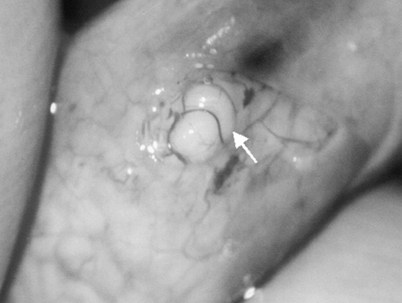

This method, originally described as the triangulation technique, was introduced by Berger (1998). There are several advantages of the methods over previous techniques (see Table 22–3) (Goldstein, 1999). The setup is identical to that for the classical end-to-side vasoepididymostomy. After the vas is fixed to the opening in the epididymal tunica, six microdots are placed on the cut surface of the vas in an identical fashion to that described for vasovasostomy. The epididymal tubule selected is dissected with blunt microscissors and the micro needle holder until it is free of surrounding tissue and prominent. The tubule is then stained with indigo carmine. Using 10-0 monofilament nylon sutures approximately 2 inches in length, double armed with 70-µm diameter fish hook–shaped tapered needles, three sutures are placed in the epididymal tubule in a triangulation fashion. The apex of the triangle faces the inferior edge of the vasal mucosa. The needles are not pulled through but left in situ, creating a triangle of needles (Fig. 22–35). Using a 15-degree microknife with the blade pointing upward, a generous opening is made in the epididymal tubule in the center of the triangle created by the three needles (Fig. 22–36).

Figure 22–36 Using a 15-degree microknife with the blade pointing upward, a generous opening is made in the epididymal tubule in the center of the triangle created by the three needles.